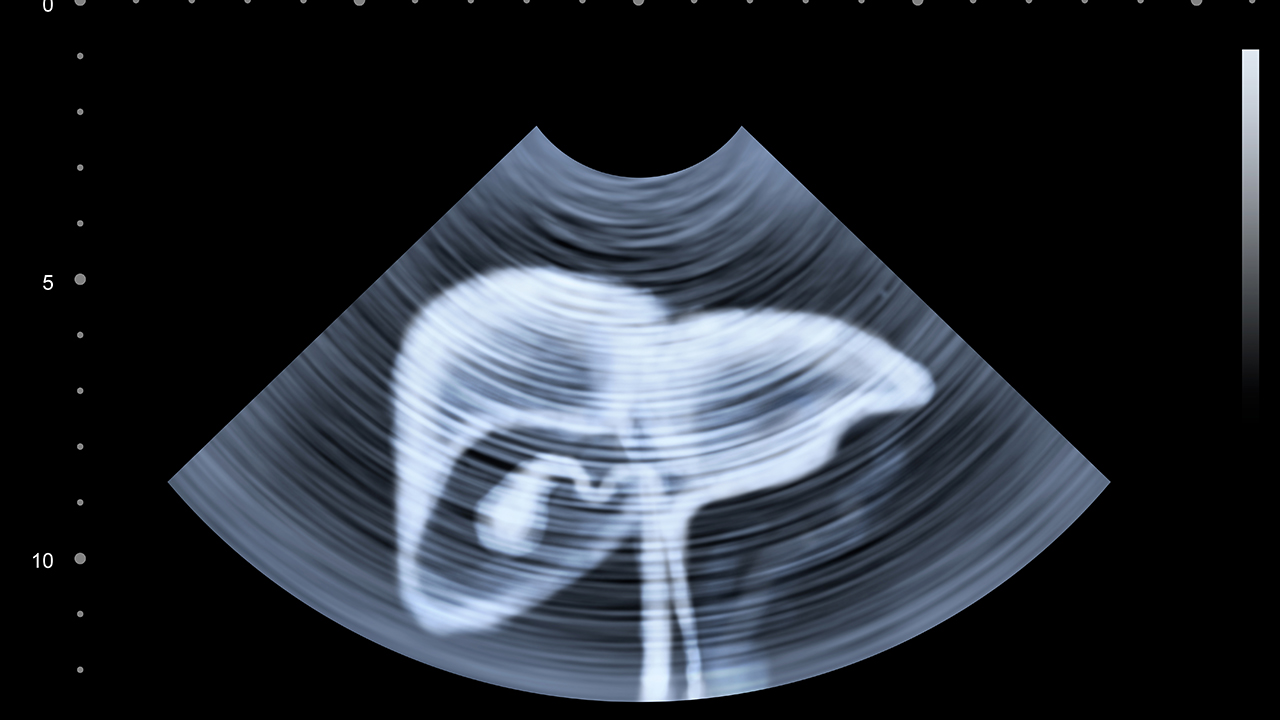

肝癌的预防与健康管理至关重要。对于高危人群,如慢性乙肝患者、肝硬化患者等,应定期进行肝脏超声和甲胎蛋白检查,以便早期发现肝癌。日常生活中应避免酗酒,减少黄曲霉素的摄入,保持良好的饮食习惯和作息规律。对于已确诊的肝癌患者,应积极配合治疗,保持良好的心态,定期复查,及时发现病情变化。同时,家属应给予患者充分的心理支持,帮助其树立战胜疾病的信心。